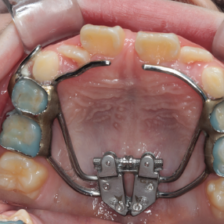

だらだらと長期間治療をするのではなく、ベストなタイミングを見計らい、一気に治療を終わらせます。